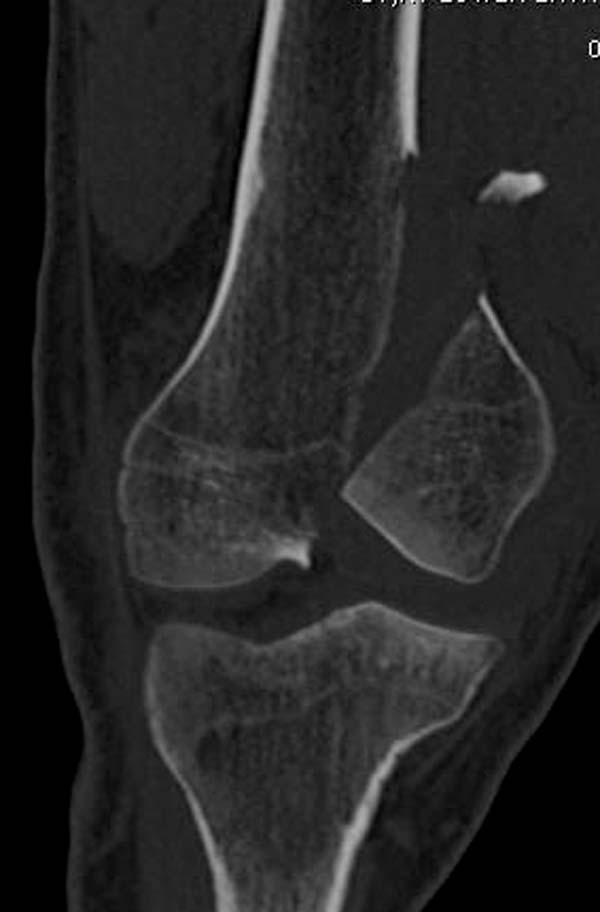

[Ortho] Нелеченный перелом Hoffa

Здесь представлены различные варианты фиксации перелома, а также снимки

комбинации перелома с повреждением хряща (12-19). Пластика хряща

OsseoFit и установка custom made plate.